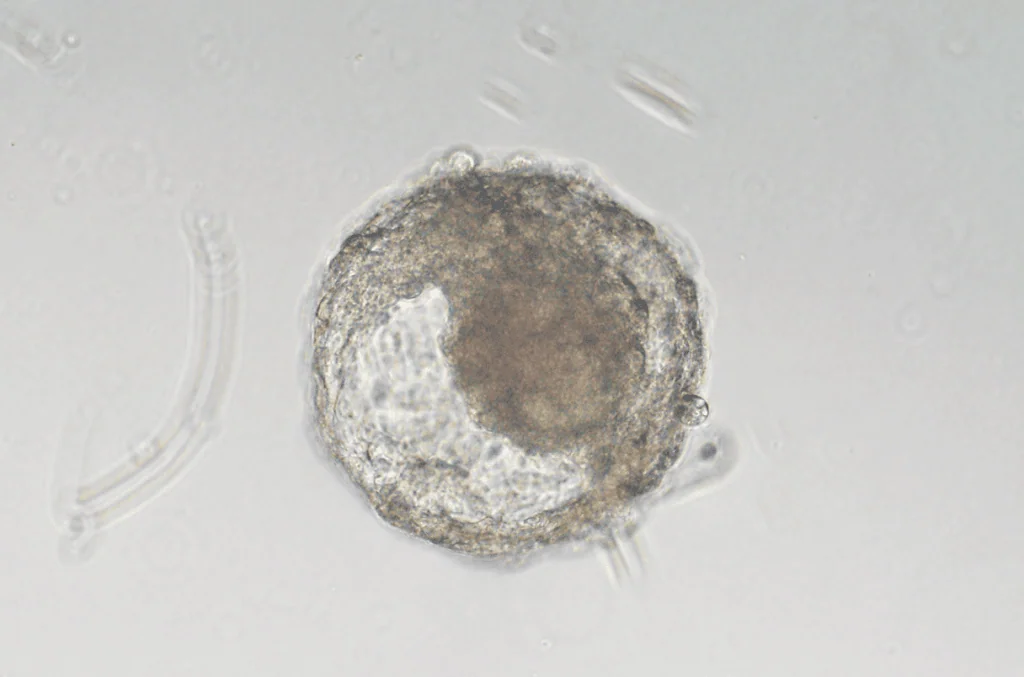

O processo utilizado para produzir o embrião sintético dependeu não só dessas células embrionárias, mas também de um esforço para as “convencerem” a formarem o que seria o estágio inicial de um organismo humano. Os pesquisadores, aliás, ressaltam esse ponto, por argumentarem que se trata muito mais de um modelo de embrião que um organismo idêntico ao gerado no encontro de um espermatozoide com um óvulo, como acontece naturalmente.

Porém, esse avanço traz uma característica peculiar ao embrião em questão. Por ser produzido com uso de células cultivadas a partir de um organismo em fase inicial, criado de forma natural, o resultado não pode ser considerado inteiramente sintético. Ou seja, ele seguiu uma formação semelhante a que acontece num útero humano, além de dar chances de evitar o uso de fertilização in vitro.

A estrutura do embrião criado por Żernicka-Goetz não contém coração e nem um cérebro em desenvolvimento, mas ele ganha uma importância para a comunidade científica por ter células de outros órgãos. Um exemplo importante é a presença de células do saco vitelino, que faz parte da formação do ventre de um bebê em gestação, sendo crucial para dar origem a órgãos reprodutivos e outras partes do corpo, como o intestino.